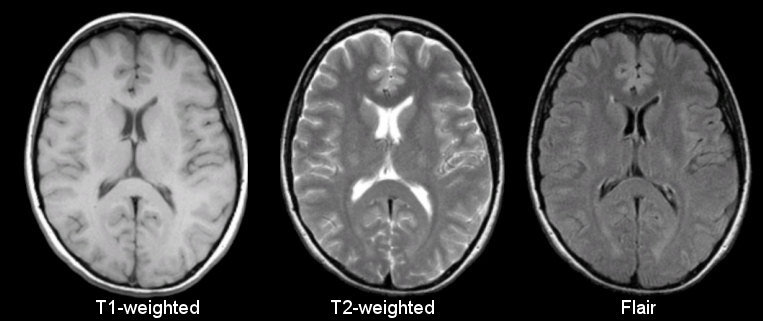

MRI T1 image characteristics + uses

1 tissue type is bright (fat) Anatomical MRI is T1 weighted Best for looking a brain structure

MRI T2 images characteristics + uses

2 tissue types are bright (fat + water) Functional MRI is T2 weighted Ideal for tissue oedema